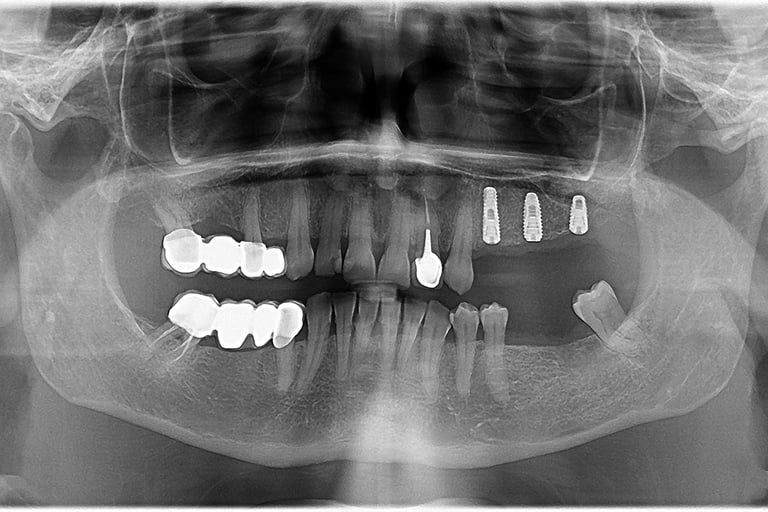

Reabilitare orala prin inserare a 3 implanturi dentare la nivelul cadranului II. In acelasi timp chirurgical s-a realizat aditie osoasa prin elevatia mucoasei sinusale in vederea asigurarii suportului osos necesar aplicarii implantului posterior.

Reabilitare implantara in cazul unor dinti restanti irecuperabili, cu mobilitate severa. Dupa extractia atraumatica a dintilor compromisi, tratamentul continua cu inserarea implanturilor dentare. In prealabil, in urma cu 6 luni s-a realizat aditie osoasa prin sinus lift extern la nivelul cadranului II, tehnica chirurgicala care ne-a permis inserarea implanturile posterioare.